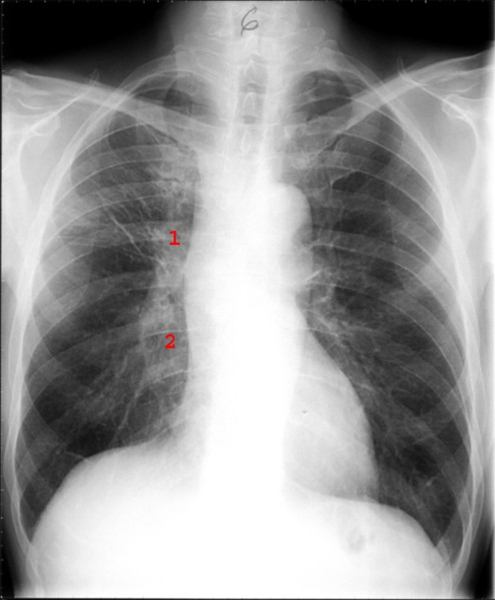

Småcellet anaplastisk carcinom, efter behandling

Efter cytostatikabehandling.

Markerede lymfeglandler i hilus på højre side (1 og 2). Atelektasen er svundet og der persisterer kun enkelte fibrøse strøg i højre overlap.